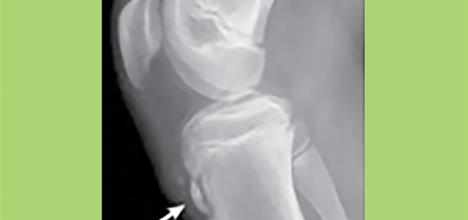

Osgood-Schlatter is a common condition in young athletes that refers to irritation of a growth plate at the knee. It typically occurs in active teens during their growth spurt and resolves after the bone stops growing.

Children have growth plates called apophyses where muscles and tendons attach. The patellar tendon of the knee connects the knee cap quadriceps (thigh) muscles to the shin bone at the tibial tubercle (bump below the knee). This growth plate is attached to the shin bone by cartilage and is subject to stress from overuse when the quadriceps muscles repetitively pull while running or jumping.